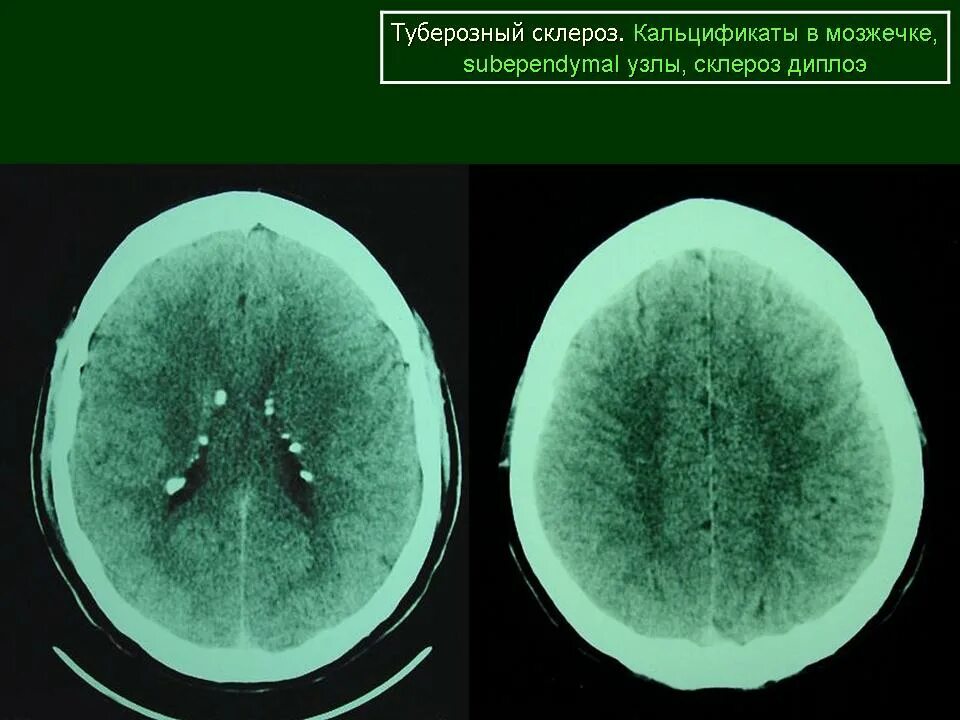

Туберкулезный склероз